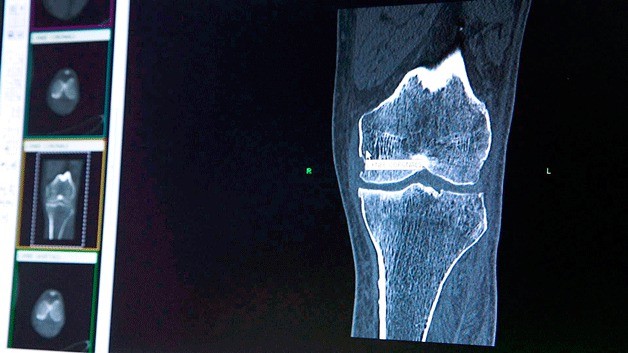

Kirkland doctor can make patients a new knee with 3D imaging

A Kirkland-based surgeon is among the first in the country to utilize new technology allowing them to mold custom knees for patients.

For Dr. Vincent Santoro, a surgeon at the Evergreen Health Orthopedics and Sports Care, the 3D imaging technology provides a wide range of benefits to patients requiring knee replacement surgery, while so far having little to no downsides.

The 3D printing technology enables Santoro to have a wax mold created within a few weeks after the initial scan which forms the metal sections of the entire knee.

One of the major improvements the precision of the imaging technology provides is that it makes it possible for surgeons to preserve sections of the patient’s knee unaffected by arthritis. This can prevent misalignments with the new knee or other complications.

Another advantage is that it prevents post-surgery issues with the replacement knee. The imaging makes for a more precise replacement knee than traditional methods in which the replacement can either be too small, too big, or not perfectly fitted to the patient. Most knee implants come in only a limited range of sizes and can prove problematic for patients whose knee fits in-between two sizes.